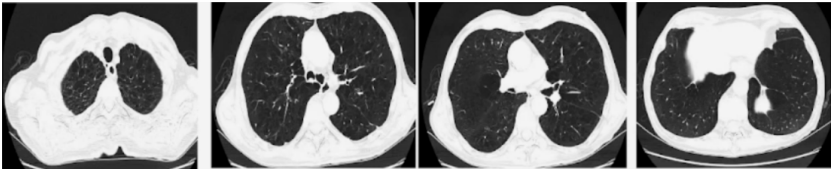

6月11日急诊胸部CT:气管插管术后;两肺多发斑片条索状高密度影,炎症可能;两肺散在陈旧灶;两侧胸膜局部增厚;两侧少量胸腔积液伴两下肺膨胀不全;两肺肺气肿,伴肺大泡;纵隔多发小淋巴结;所示胃壁见金属密度影(图2)

图片

图2  患者胸部CT(6月11日)